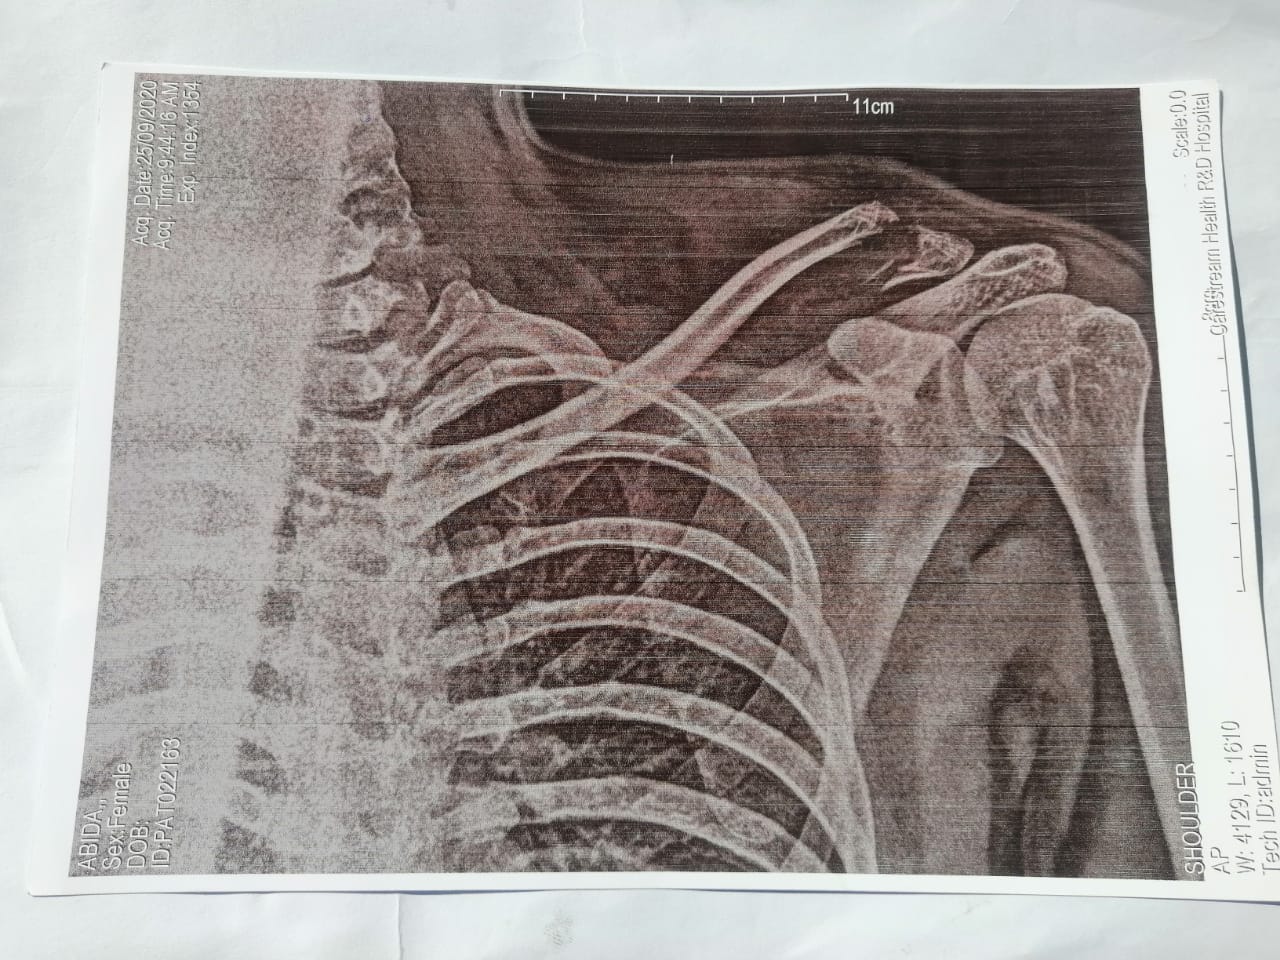

Asking for Brother, Male, 24 years old, Sheikhupura

Please guide if this needs surgery not not. Its been 1 month, and the fracture is not healing yet.

this is non healing displaced fracture of clavicle it needs urgent reduction so it can heal if reduction don't work then fixation most likely internal fixation will be required.